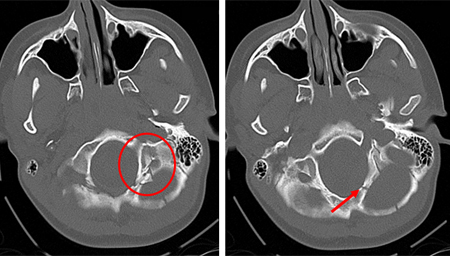

[Figure caption and citation for the preceding image starts]: Axial CT scan demonstrating an open non-depressed linear skull fracture (arrow) associated with pneumocephalus (circle) [Citation ends].

[Figure caption and citation for the preceding image starts]: Axial CT scan showing non-depressed linear skull fracture (arrow) of the skull base involving the foramen magnum. This injury pattern is concerning for associated spinal fracture, cord injury, and blunt cerebrovascular injury [Citation ends].